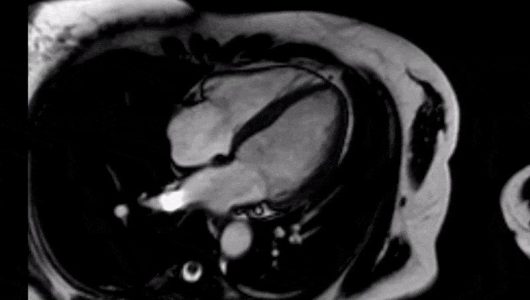

Η μαγνητική τομογραφία καρδιάς (Cardiac Magnetic Resonance, CMR) είναι μια εξειδικευμένη, μη επεμβατική, απεικονιστική μέθοδος που επιτρέπει ταυτόχρονα τη μελέτη της ανατομίας, την ακριβή εκτίμηση της λειτουργίας και τον χαρακτηρισμό των ιστών της καρδιάς. Είναι ασφαλής, ανώδυνη, δεν απαιτεί ειδική προετοιμασία και δεν εκθέτει τον ασθενή σε ιονίζουσα ακτινοβολία. Η κλινική της σημασία φαίνεται από τις ολοένα και περισσότερες εξετάσεις που διενεργούνται παγκοσμίως.

Ο μαγνητικός τομογράφος χρησιμοποιεί μαγνητικά πεδία και ραδιοκύματα για την παραγωγή τρισδιάστατων δεδομένων που μεταφράζονται σε εικόνες υψηλής ευκρίνειας από έναν υπολογιστή με ειδικό λογισμικό. Στις περισσότερες περιπτώσεις χορηγείται σκιαγραφική ουσία (γαδολίνιο) για τη λήψη περαιτέρω πληροφοριών.